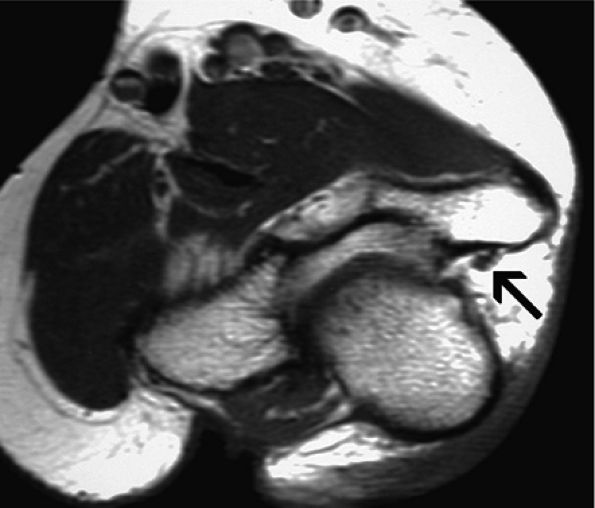

|

FIGURE 12.25 ● Absent arcuate ligament. Axial T1-weighted image demonstrates absence of the arcuate ligament incidentally noted in this asymptomatic patient. The ulnar nerve is normal (arrow).